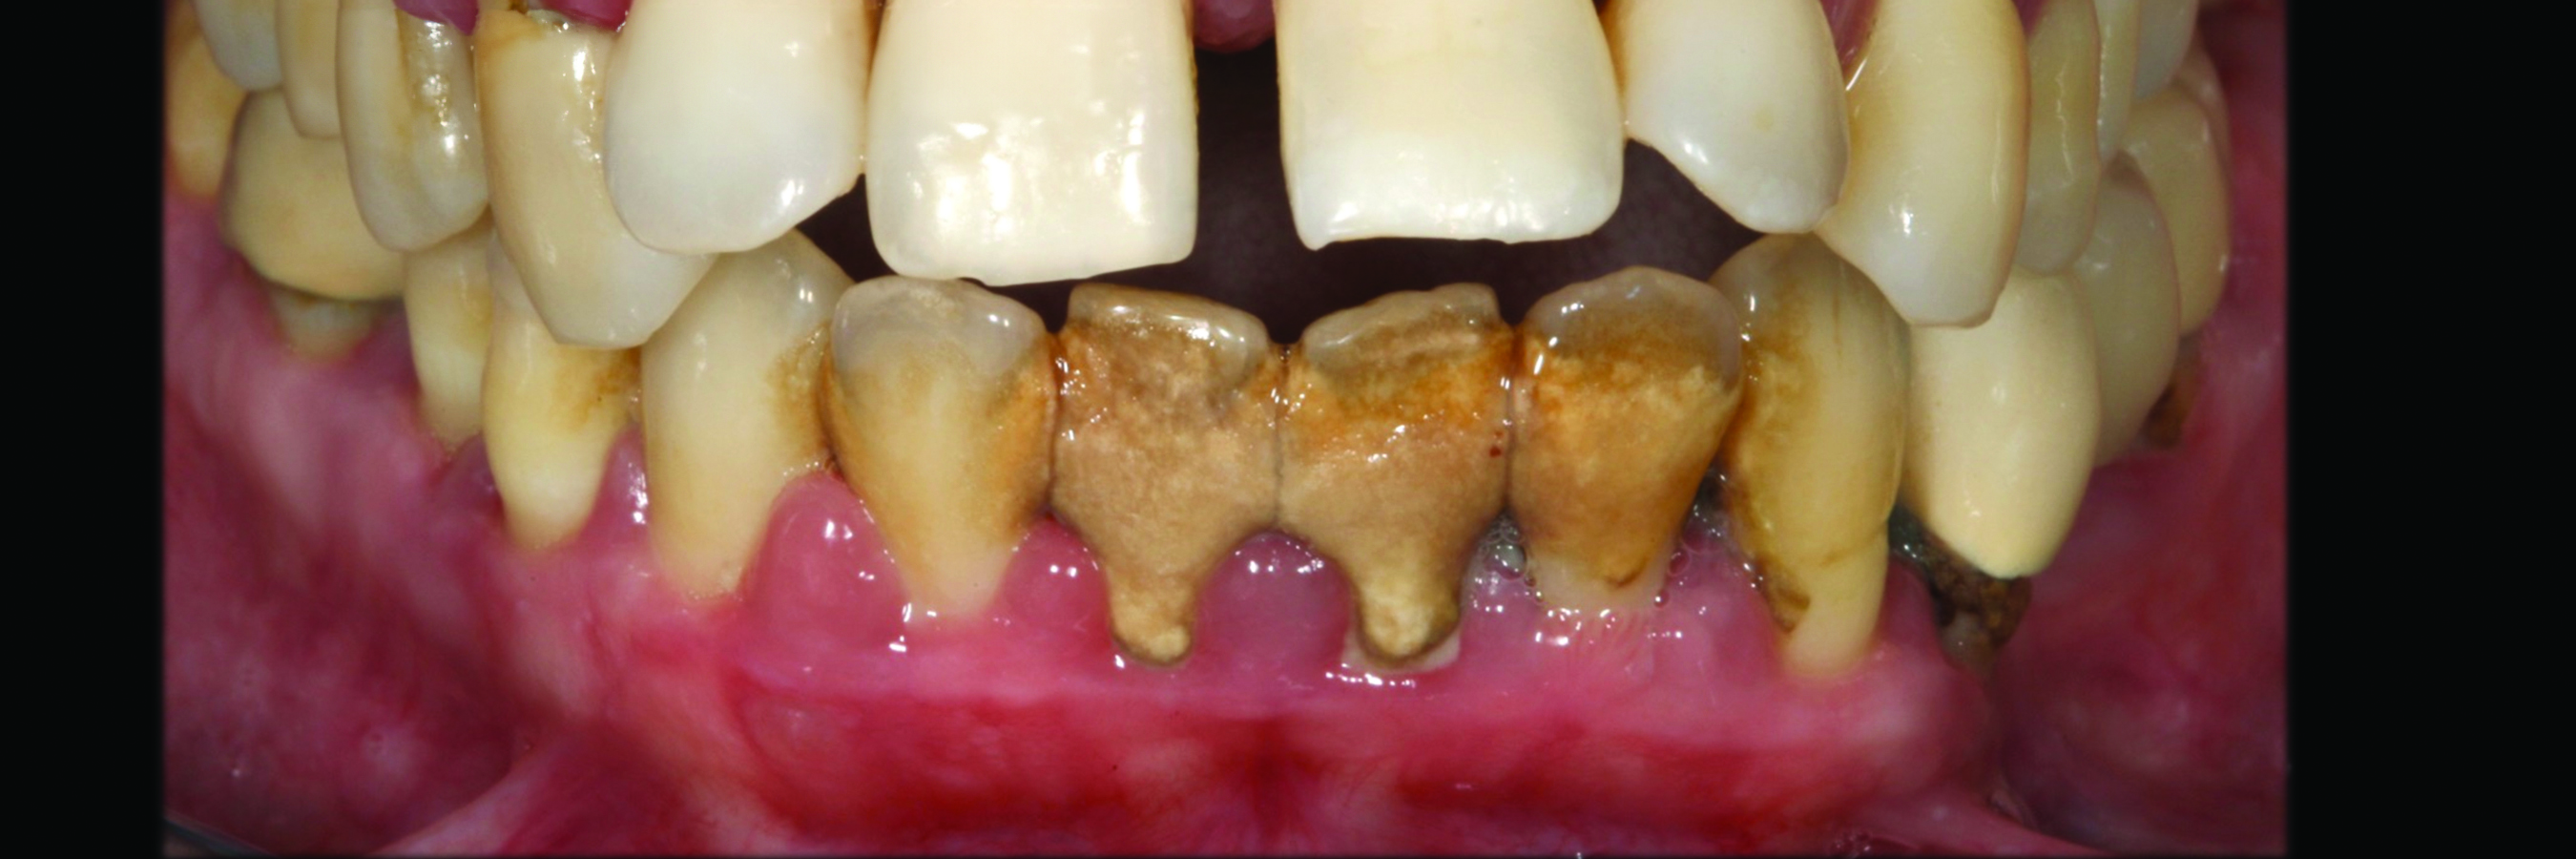

Fig 4. Case 1. Initial presentation of a patient with periodontitis (teeth Nos. 22 through 27). Generalized pocket depths of 5 mm to 6 mm were present.

Figure 4

Fig 5. Initial radiograph of the Case 1 patient, teeth Nos. 22 through 27.

Figure 5

Fig 6. Results of SRP demonstrated resolution of inflammation and residual probing depths of 2 mm to 3 mm, 18 years after treatment of Case 1 patient.

Figure 6